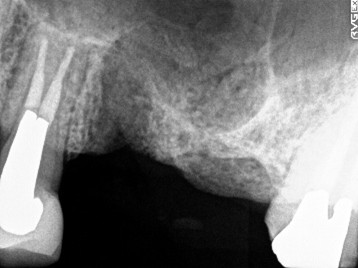

レントゲンで詳しく診てみると、虫歯が歯根のほうまで進行し、保存することができないことがわかり、抜歯しました。抜歯後、骨が大きく欠損していましたので、骨造成を行いインプラントを2本埋入しました。

所感

Before

【抜歯後】

After